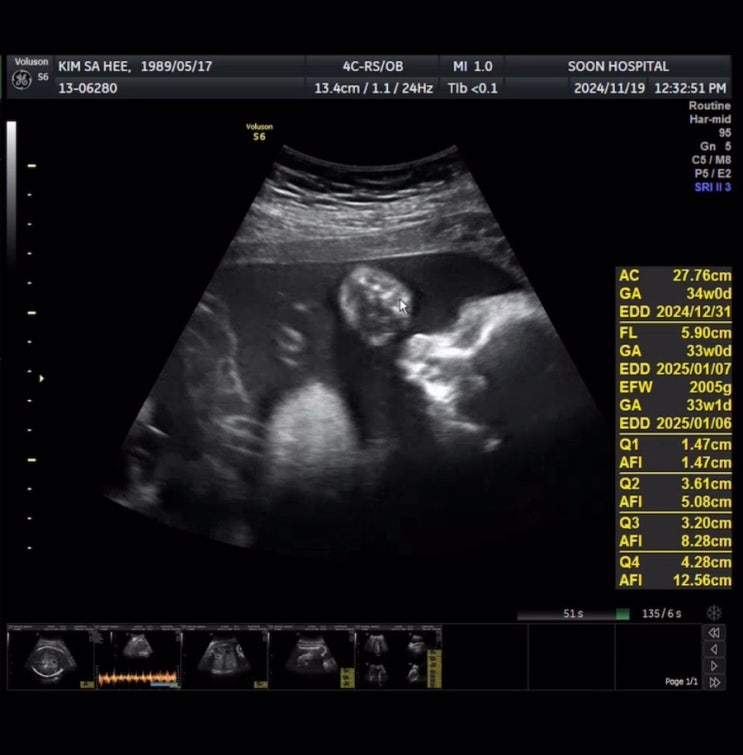

[임신 34주차] 먹고 자고 먹고 자고... 바쁜 임산부 / 애기옷 빨래 / 임산부 왁싱

[임신 32주차] 크리스마스 준비중인 부산에서의 일상 / 32주차 순병원 정기검진 / 돌아다니느라 바쁜 임산부

잘 먹고 잘 쉬고 있는 임신 9개월차 임산부 :D 다행히 한국와서 잘 먹고 다니고 있지만, 활동량이 많아서 ...